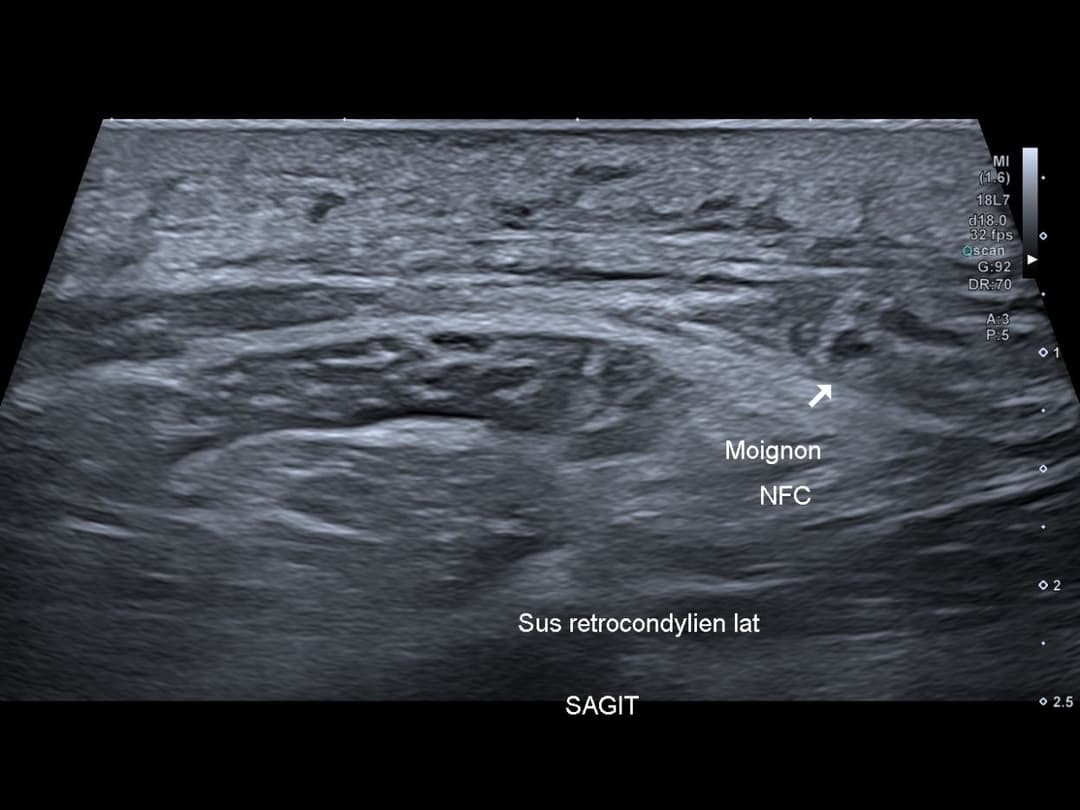

Echographie réalisé avant chirurgie pour marquage du nerf fibulaire commun.

Visualisation du moignon distal du NFC

Le nerf fibulaire commun présente un important épaississement dans sa portion rétro-condylienne en amont de l’interligne articulaire avec rétraction.